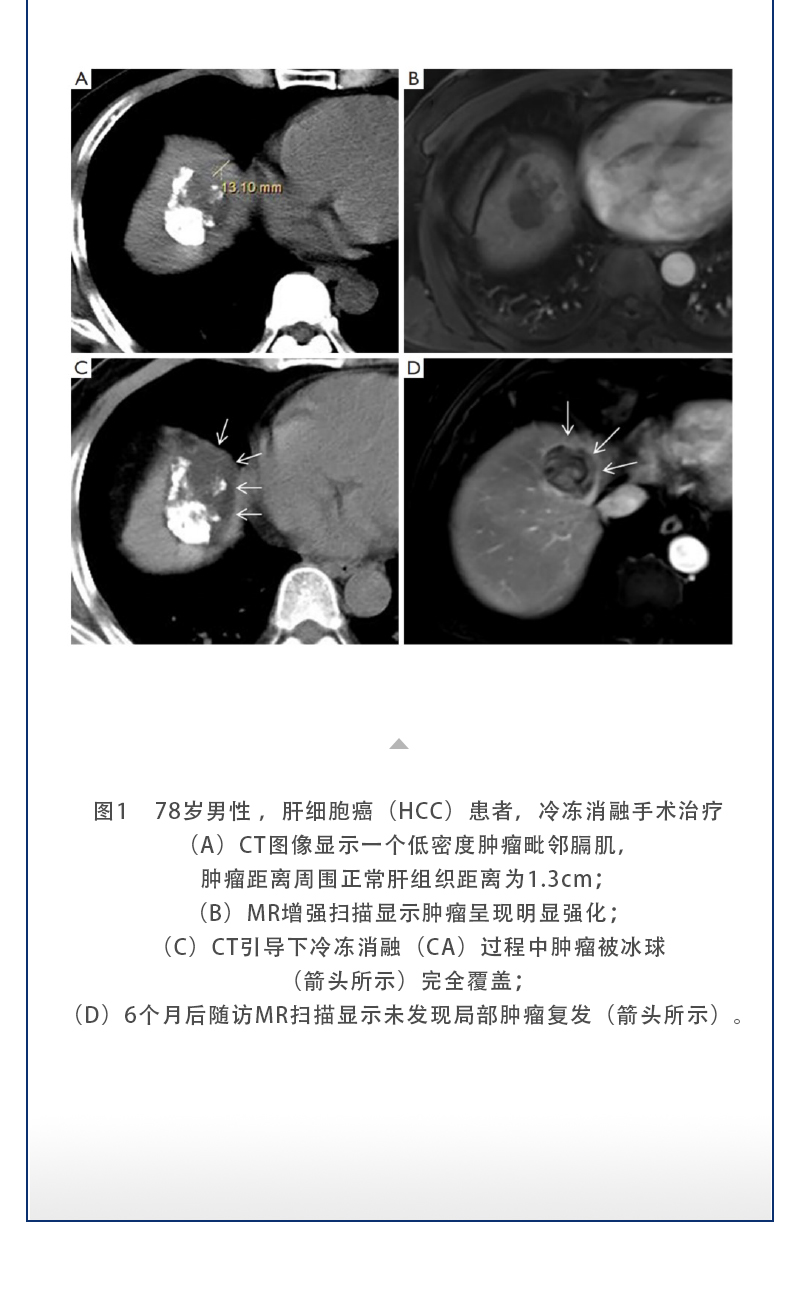

ELF ? 復(fù)合式冷熱消融系統(tǒng)